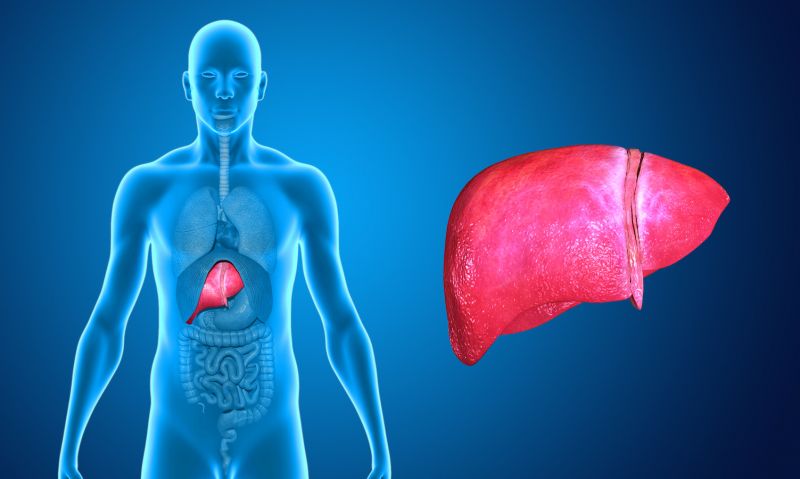

تنظيف الدم والكبد والكلى بوصفة طبيعية

وصفة طبيعية خاصة في تنظيف الدم والكبد والكلى سهلة الإعداد تمكنكم من تنظيف الدم والكبد والكلى ولا يمكن للإنسان أن يعيش حياة هانئة في ظل إعتلال أي من أحد هذه الأمور لذ